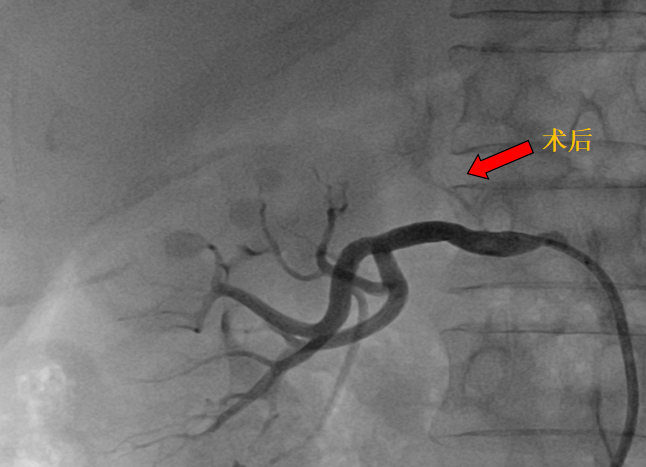

近期,黔南州中医医院心血管内科李莲主任团队詹玉柱副主任医师成功完成黔南首例经皮选择性肾上腺动脉栓塞术(SAAE)。手术顺利,患者恢复良好,标志着黔南州中医医院在继发性高血压的微创介入治疗领域取得重要突破,为区域该类患者提供了更精准、安全、微创的全新治疗。

黔南州中医医院心内科高血压亚专科团队为其进行了系统的继发性高血压筛查,肾上腺CT增强提示右侧肾上腺腺瘤(约12mm×7mm),伴左侧肾上腺增生,确诊为原发性醛固酮增多症所致高血压。

双侧肾上腺静脉取血提示右侧肾上腺为优势分泌侧。经与泌尿外科充分术前讨论,鉴于其右侧腺瘤体积较小,且合并左侧增生,外科手术切除腺瘤较困难,且患者拒绝外科手术治疗,故予右侧肾上腺动脉栓塞治疗。

(历时30分钟成功施行经皮选择性肾上腺动脉栓塞术)

术后第一天,患者仅服一种降压药,血压便控制理想,复查醛固酮、醛固酮/肾素比值均明显降低,血钾恢复至正常范围。术后第三天,患者康复出院。